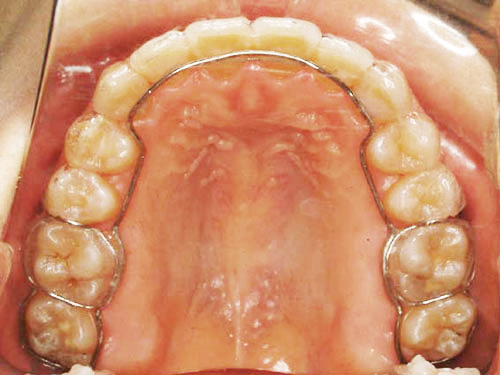

OH型ワイヤーリテーナー:取り外し式

ベッグリテーナーの進化型リテーナーで、内側のプラスチック部を一本のワイヤーに置き換えて、舌のスペースを広くし、しゃべりやすくなっています。外側のワイヤーには透明のプラスチックバー(QCMリテーナーワイヤー)を使用し、装着していても目立ちません。基本的に食事の際は外しますが、飲み物や簡単なものなら、着けたままでも構いません。SHRより保持力が強く、後戻りで狭窄しやすい上顎の保定に適しています。